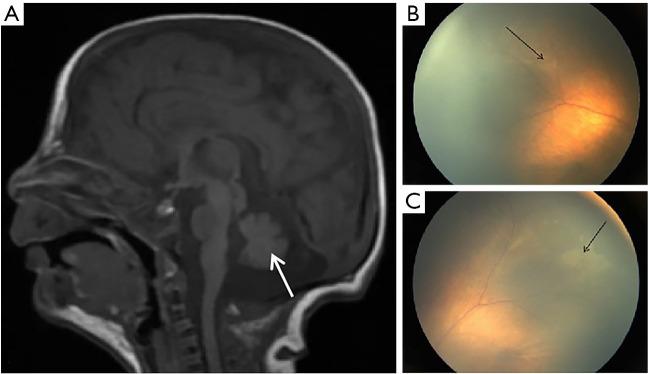

A newborn was diagnosed with a previously unreported truncating mutation in ASXL2 (NM_018263.6) at 21 days and the clinical characteristics of all probands with ASXL2-related SHAPNS was reported in the literature. He had persistent hypoglycemia caused by inappropriate insulin levels and achieved stable glucose levels after octreotide treatment. Magnetic resonance imaging (MRI) revealed a small cerebellum, and fundoscopy showed bilateral retinal paving-stone-like white lesions. The results of trio-based whole exome sequencing (WES) were returned on the 21st day of life, and a heterozygous de novo truncating pathogenic c.1792C>T (p.Gln598*) variant in exon 11 of the gene was identified. The clinical features of our patient and another 10 probands with -related SHAPNS reported in the literature were included in this review. More than half shared recognizable clinical features, including hypertelorism (11/11), broad nasal tip (10/11), arched eyebrows (9/11), a large V-shaped glabellar nevus flammeus on the forehead (9/11), low-set ears (8/11), posteriorly rotated ears (7/11), proptosis (6/11) and deep palm creases (6/11). Major clinical issues included feeding difficulties (10/11), developmental delay (10/11), skeletal and/or extremity abnormalities (8/11), progressive macrocephaly (8/11), hypotonia (8/11), hypoglycemia (6/11) and seizures (6/11). Neurodevelopmental regression was possible in patients (2/11) with normal MRI findings who later developed nonfebrile seizures.

We present a newborn diagnosing the SHAPNS by trio-WES, which is the earliest age of diagnosis. The application of octreotide for hypoglycemia, the small cerebellum and bilateral paving-stone-like white lesions of the retinas are described for the first time in an individual with -related SHAPNS. Additional clinical reports of neonates with damaging ASXL2 variants are necessary to verify the mechanism and optimal treatment of ASXL2-related hypoglycemia, neurological damage and optic impairment. Neurological, endocrinological, ophthalmological, and rehabilitative follow-ups of these patients are necessary and important.

一名新生儿在21天时被诊断出ASXL2(NM_018263.6)存在先前未报道的截短突变,并报道了文献中所有与ASXL2相关的沙希 - 佩纳综合征先证者的临床特征。他因胰岛素水平异常导致持续性低血糖,在奥曲肽治疗后血糖水平稳定。磁共振成像(MRI)显示小脑较小,眼底检查显示双侧视网膜铺路石样白色病变。基于三联体的全外显子组测序(WES)结果在出生后第21天返回,在该基因第11外显子中鉴定出一个杂合的新发截短致病变异c.1792C>T(p.Gln598*)。本综述纳入了我们患者以及文献中报道的另外10例与ASXL2相关的沙希 - 佩纳综合征先证者的临床特征。超过一半的患者具有可识别的临床特征,包括眼距增宽(11/11)、鼻尖宽大(10/11)、眉弓高拱(9/11)、前额有大的V形火焰状眉间痣(9/11)、耳位低(8/11)、耳向后旋转(7/11)、眼球突出(6/11)和手掌深纹(6/11)。主要临床问题包括喂养困难(10/11)、发育迟缓(10/11)、骨骼和/或肢体异常(8/11)、进行性巨头症(8/11)、肌张力低下(8/11)、低血糖(6/11)和癫痫发作(6/11)。MRI检查结果正常但后来出现无热惊厥的患者(2/11)可能发生神经发育倒退。

结论